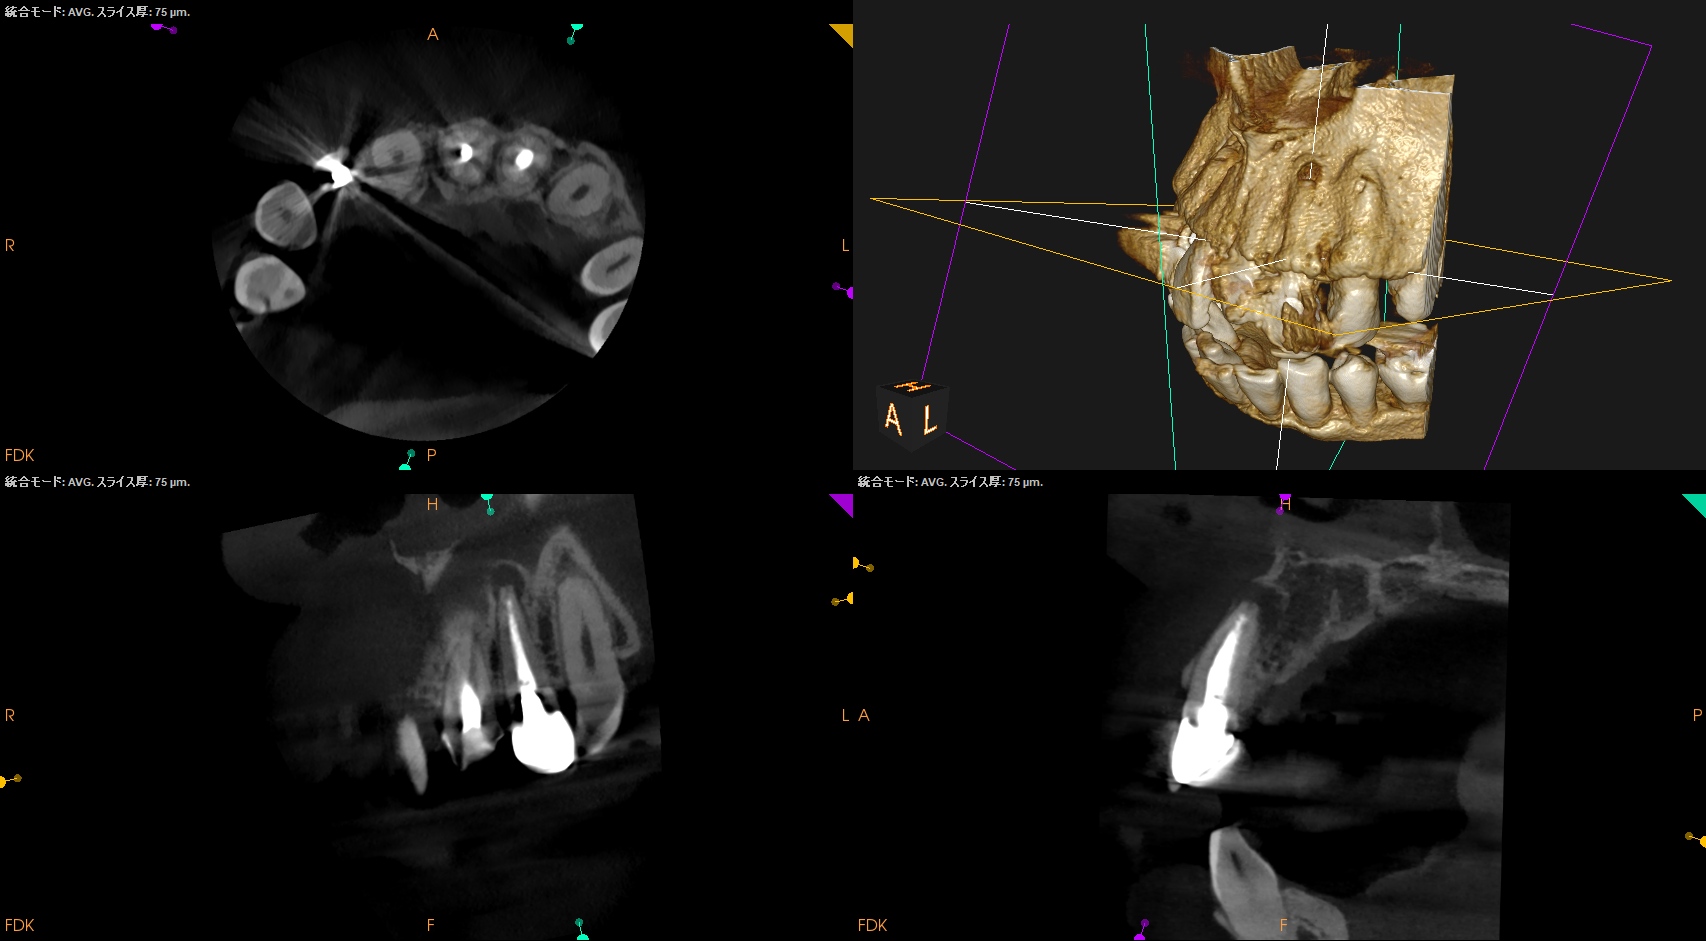

CBCT(2025.1.16)

#7

頬側皮質骨が消失している。

これが圧痛の原因だろう。

#10

#10も#7に同じである。

根管形成・当該部位への根管充填がほぼなされていないように見えることから, 再根管治療へ移行した。